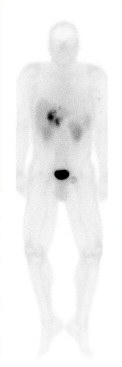

Somatostatin-

Auf Grund der erwähnten einfachen Diagnosestellung der NFPT durch CT und US spielt die Endosonographie (EUS), bei weitem nicht die bedeutende Rolle, die ihr bei der Lokalisation der kleineren funktionellen endokrinen Pankreastumore gewiss. Die SRS hat bei NFPT eine Sensitivitätsrate von 80-

Limitierend ist, dass durch die SRS oft keine Aussage über die exakte anatomische Lokalisation getroffen werden kann. Dennoch ist die SRS nicht nur zur Abgrenzung gegenüber exokrinen Pankreastumoren die wesentliche Untersuchung, sondern auch allen anderen Untersuchungen im Staging der Erkrankung überlegen.